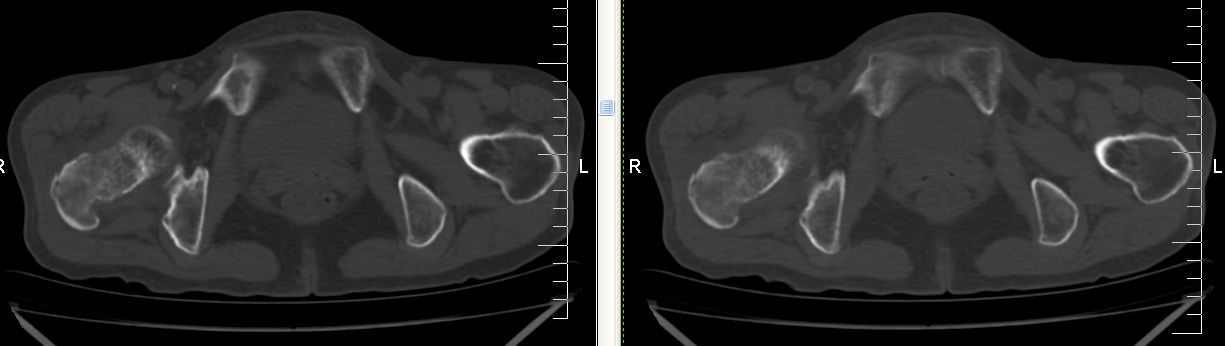

以下是引用余辉在2007-12-5 17:25:00的发言:[br]右侧股骨颈及粗隆区略显膨胀,密度增高略呈不均匀毛玻璃样改变,骨皮质毛糙,考虑1骨纤2骨髓瘤3转移瘤,建议上传软组织窗